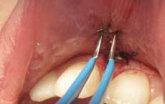

OXYSAFE® – Innovative Technologie auf Aktivsauerstoffbasis zur Behandlung von Parodontalerkrankungen

Patientensituation nach erfolgter Therapie mittels Metronidazol, CHX Chips, aPDT und anderen Maßnahmen nach dem 3. Recall

Applikation des OXYSAFE Gels in situ Patientensituation 3 Wochen nach Beginn der Sauerstofftherapie mittels OXYSAFE

OXYSAFE® Professional Gel und Liquid

Zur nachhaltigen Unterstützung in der Behandlung von Parodontitis und Periimplantitis

• Gel und Mundspülung mit aktiver Sauerstofftechnologie

• Schnelle Reduktion der Taschentiefe

• Taschendesinfektion und beschleunigte Wundheilung

• Einfache und präzise Applikation

Anwendung von OXYSAFE®

Parodontitis ist die häufigste Erkrankung in der Mundhöhle. Nach Schätzungen sind bis zu 70% der Bevölkerung betroffen. Unzureichende Mundhygiene, Rauchen, Diabetes und genetische Veranlagung sind unter anderem die Faktoren, die zum Auftreten einer Parodontitis führen. Zu den klinischen Merkmalen zählen Zahnlockerung, Taschenbildung mit Knochenabbau, bei gleichzeitigem Vorhandensein von Entzündungszeichen, die sich in Blutungen, Ödemen, häufig mit Pusabfluss und fast immer unangenehmem Atem äußern. Die Hauptursache ist eine bak terielle Infektion. Taschen mit einer Tiefe von mehr als 3 mm erfordern eine Behandlung. Der Behandlungsplan beginnt mit einer nicht-chirurgischen Parodontaltherapie, die aus supra- und subgingivaler Reinigung besteht. Der Goldstandard in der nicht-chirurgischen Parodontalthera pie ist die sogenannte Wurzelreinigung und -politur, eng. Scaling and Root Planning (SRP). Die Ablagerungen von subgingivalen Plaques und Zahnstein werden entfernt. Somit wird die An zahl der parodontalpathogen Keime (Aggregatibacter actinomycetemcomitans, Porphyromonas gingivalis, Prevotella intermedia), die vielfach im Plaque vorhanden sind, deutlich reduziert. Hauptziel der kausalen Therapie ist es, die Entzündung des Zahnhalteapparates zu reduzieren und die Reparatur und Regeneration der Stützstrukturen des Zahnes zu fördern. Bei der genera lisierten, fortgeschrittenen chronischen Parodontitis und bei der aggressiven Parodontitis ist der Einsatz von Antibiotika unterstützend möglich. Die mechanische Entfernung von subgingivalen Ablagerungen und das Debridement von Taschen sind sehr wichtige Bestandteile der Behand lung, um den bakteriellen Biofilm zu entfernen.

In der Parodontitistherapie finden chemische Wirkstoffe wie Wasserstoffperoxid, Jod, Chlorhe xidin, photodynamische Therapie und schließlich Präparate auf Aktivsauerstoffbasis ihren Platz. Chlorhexidin ist seit vielen Jahren bei Parodontaltherapien im Einsatz, es führt jedoch häufig zu Nebenwirkungen wie Geschmacksverlust, Verfärbungen der Zähne und Zunge. Zusätzlich sind die Moleküle von Chlorhexidin oft zu groß, um den Biofilm ausreichend zu durchdringen. Zudem ist eine häusliche Anwendung einer Mundspüllösung nur für zwei Wochen empfohlen. Eine Al ternative, die seit 2017 auf dem Markt ist, ist OXYSAFE. Es ist eine patentierte Technologie auf Basis eines Kohlenwasserstoff-Sauerstoff-Komplexes, die durch Kontakt mit der Mundschleimhaut akti viert wird. Dabei wird aktivierter Sauerstoff im behandelten Bereich freigesetzt und die anaerobe Bakterienflora erheblich reduziert. Vereinfacht ausgedrückt werden Proteine im Biofilm oxidiert, was zu einer verbesserten Biofilmpermeabilität tief in der Parodontaltasche führt. Anaerobe Bak terien haben keine Nährstoffbasis, lösen sich in den Zellwänden auf und werden zerstört. OXYSA FE ist in zwei verschiedenen Viskositäten, in flüssiger und gelartiger Form, erhältlich. OXYSAFE als Gel für den Gebrauch in der Praxis während der Parodontitistherapie, das lange in der Tasche ver bleibt und so die frühzeitige Neuansiedlung von Bakterien verhindert. Zur Aufrechterhaltung des Behandlungserfolges und zur chemischen Kontrolle der Plaque bekommt der Patient OXYSAFE in flüssiger Form als Mundspüllösung verordnet, die er Zuhause gemäß der herkömmlichen Mund hygiene zweimal täglich zur Spülung nutzt. Darüber hinaus wirkt sich die sauerstoffangereicherte Mikroumgebung positiv auf die Heilung des geschädigten Zahnhalteapparates aus. OXYSAFE ist antibakteriell und fungizid. Die Mukosazellen und Osteoblasten bleiben intakt. OXYSAFE ist nicht zytotoxisch und enthält keine Peroxide und freien Radikale.

Fallbericht

Ein 55-jähriger Patient kommt zur ersten Untersuchung in die Klinik der Abteilung für Parodon tologie des Klinischen Krankenhauses Zagreb. Er ist Raucher und hat keine systemischen Erkran kungen. Die Begutachtung des Orthopantomogramms und klinische Untersuchung weisen auf eine Parodontitis hin.

VorherNachher

Beispielhaft nun die Anwendug von OXYSAFE am Frontzahn

11. Die Sondierungstiefe beträgt sowohl mesial als auch distal 7 mm an Zahn 11 und es liegt eine Blutung vor. Es liegt ein vertikaler Knochenverlust vor.

Reinigen der Zahnfleischtasche Erste direkte Applikation des Gels in die Zahnfleischtasche Fortsetzung der Behandlung durch den Patienten zuhause 3 täglich 10 ml Zweite Applikation des Gels in die Zahnfleischtasche und dort belassen >> Keine Antibiotika >> Kein CHX >> Über 20 Jahre klinische Erfahrung ca. 2,74 € pro Zahnfleischtasche Aktion Jetzt gratis testen!*